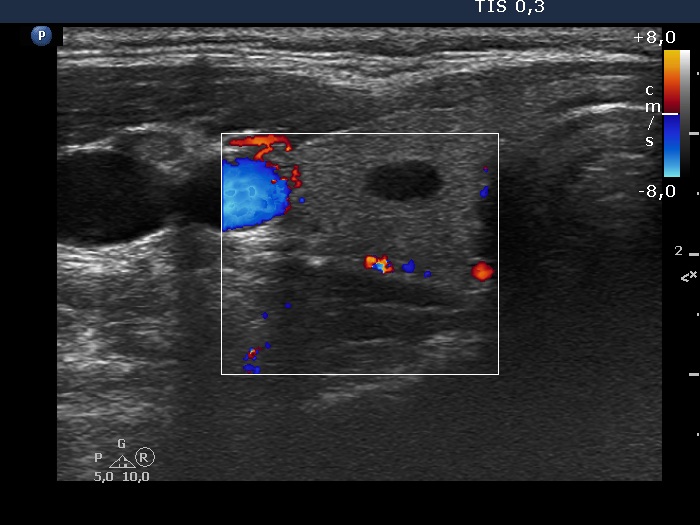

TIRADS - case 1649 (ultrasonographic picture 3)

Right lobe, longitudinal scan

Right lobe, transverse scan, color Doppler mode. The vascularization is scanty.